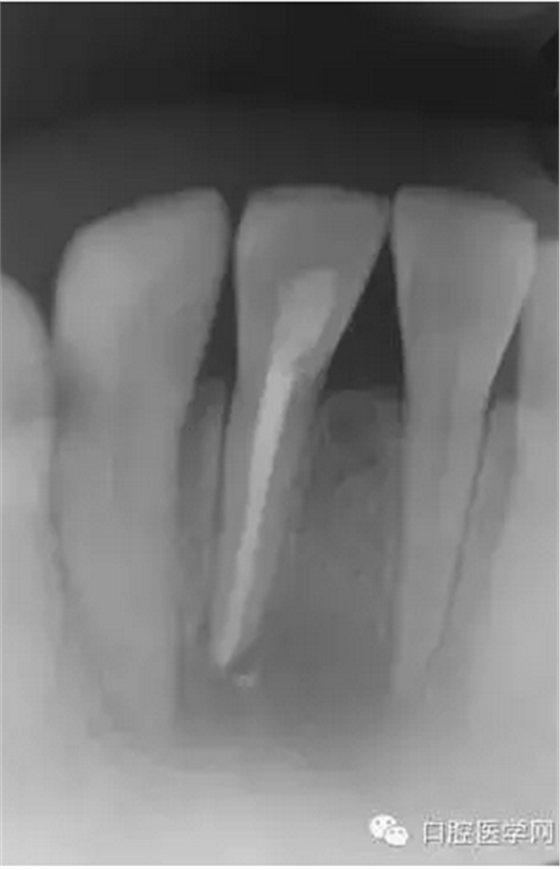

根管充填1個月后復(fù)診檢查過之后,一年后再次復(fù)診。如(圖5),可見大范圍破壞根尖周病變大部分基本治愈。

(圖 4) 根管充填1個月后

(圖 5) 根管充填約1年后